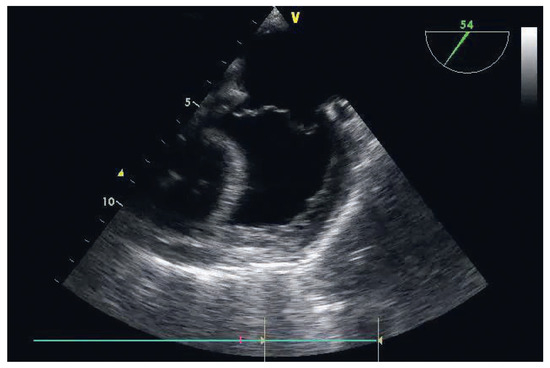

The Weak Heart: Perioperative Management

by Dominique Anne Bettex, Pierre-Guy Chassot and Alain Rudiger

Cardiovasc. Med. 2015, 18(10), 273; https://doi.org/10.4414/cvm.2015.00362 - 21 Oct 2015

Heart failure (HF) is known to be a major risk factor in perioperative care. It should be subdivided into systolic or diastolic dysfunction as well as left or right ventricular failure. The perioperative management of HF patients is complex, consisting of prevention, diagnosis [...] Read more.

Heart failure (HF) is known to be a major risk factor in perioperative care. It should be subdivided into systolic or diastolic dysfunction as well as left or right ventricular failure. The perioperative management of HF patients is complex, consisting of prevention, diagnosis and therapy. The adequacy of the perioperative management determines the late postoperative outcome and will be presented in this review. Full article

Show Figures

Figure 1